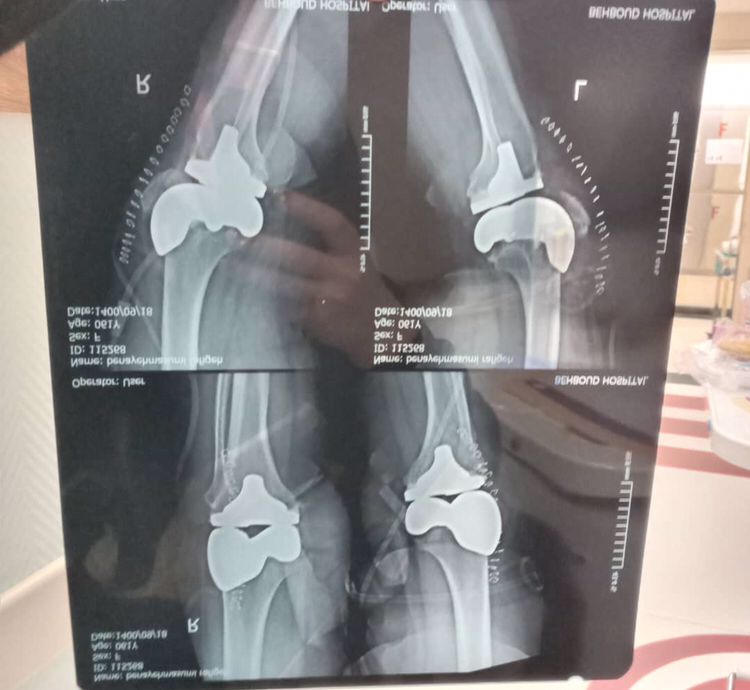

دکتر هوشمند در جراحیهای مفاصل نیز تخصص دارد. این شامل جراحیهای تعویض مفصل (مانند تعویض مفصل زانو یا لگن)، درمان بیماریهای استخوانی و مفصلی از جمله آرتروز و شکستگیهای شدید است. وی با استفاده از تجهیزات پیشرفته و تکنیکهای مدرن جراحی، فرآیند درمان را به صورت دقیق و مؤثر انجام میدهد.دلایل نیاز به مراجعه به جراح ارتوپدی